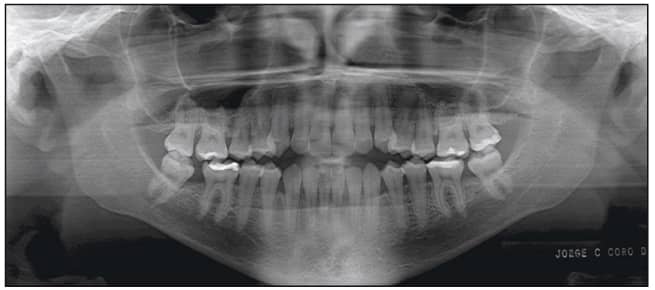

The patient, a 26-year-old female, presented with a chief complaint that she did not like her smile and was unable to bite with her front teeth. She presented with a concave profile due to an apparent midface deficiency and mandibular prognathism. She had a Class III anterior open bite malocclusion, confirmed by the cephalometric analysis (Figures 2 to 4).